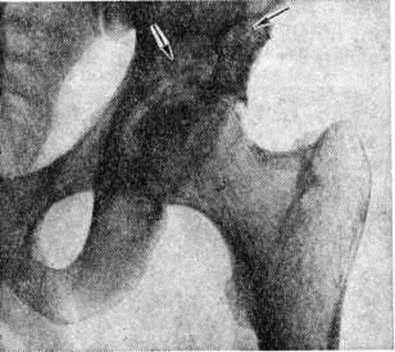

Туберкулёзный Остеоартрит диагностируется на основании регионарного остеопороза, околосуставного очага костной деструкции с неровными нечёткими контурами, сужения суставной щели вследствие разрушения суставных хрящей. В случаях поздней диагностики болезни обнаруживают контактную деструкцию в других костях, образующих сустав (рисунок 1). При туберкулёзном поражении крупного сустава первичный костный очаг на обычных рентгенограммах может не выявляться; его обнаруживают лишь с помощью томографического исследования. Диагностика туберкулёзного Остеоартрит должна подкрепляться характерной клинические, картиной и данными лабораторный исследований.

Рис. 1.

Рентгенограмма тазобедренного сустава больного туберкулёзным остеоартритом: очаг деструкции в теле подвздошной кости (указан стрелками).